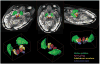

Results: Superior image resolution and contrast obtained at 7 T in vivo using susceptibility-weighted imaging dramatically improved anatomic delineation of DBS targets and allowed the identification of internal architecture within these targets. A patient-specific, 3-dimensional model of each target area was generated on the basis of the acquired images.

Conclusion: Technical developments in MRI at 7 T have yielded improved anatomic resolution of deep brain structures, thereby holding the promise of improving anatomic-based targeting for DBS surgery. Future study is needed to validate this technique in improving the accuracy of targeting in DBS surgery.